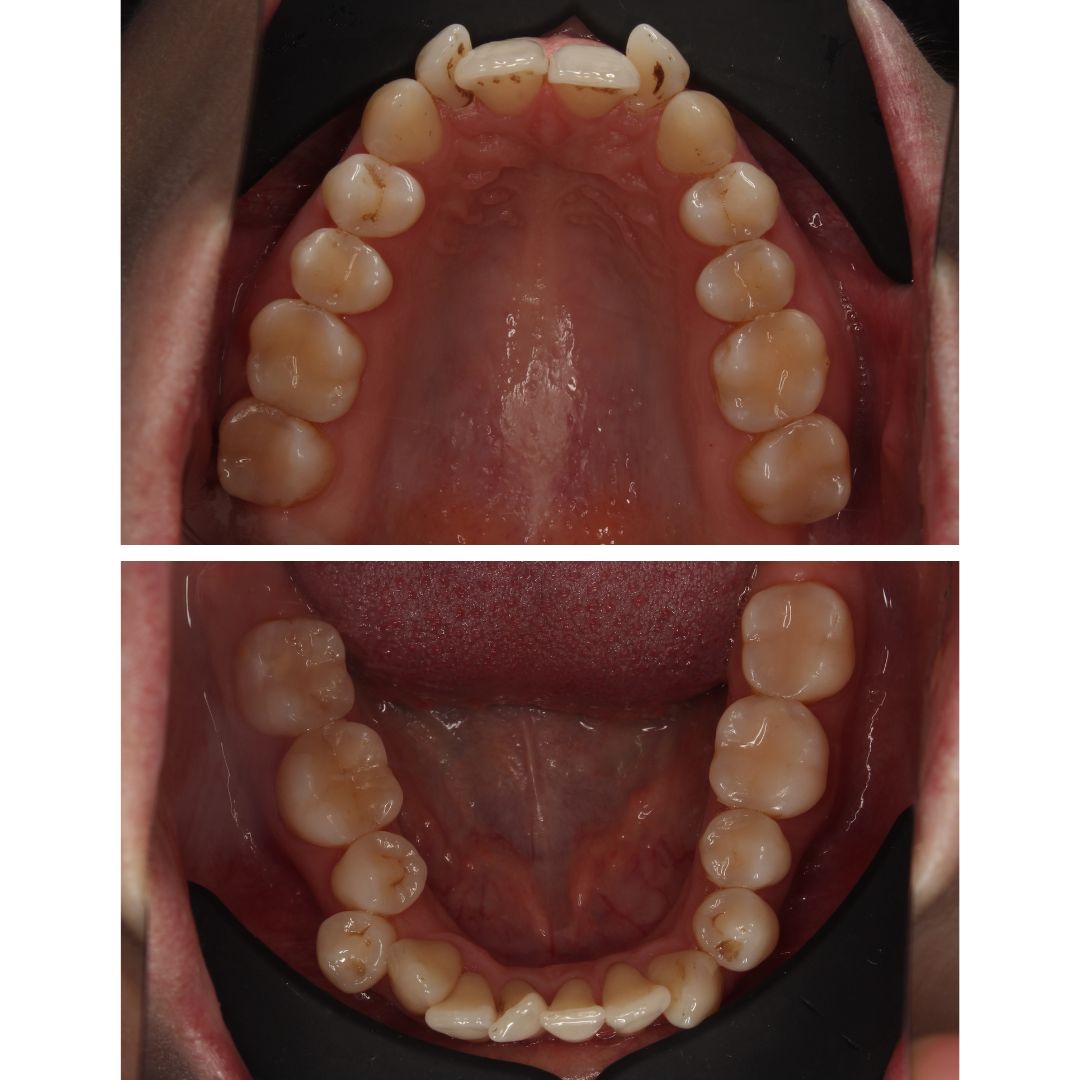

МЫ СМОГЛИ ДОБИТЬСЯ РЕЗУЛЬТАТА ПРОВЕДЯ ДИСТАЛИЗАЦИЮ – смещение жевательных зубов на верхней и нижней челюсти назад. Такое лечение проводится с установкой миниимпланататов, которые служат опорой для крепления тяги идущей к зубу или группе зубов, которые нужно сместить.

ЧЕРЕЗ 2 ГОДА ЛЕЧЕНИЯ – у пациентки ровный, красивый зубной ряд с плотными межзубными контактами 🥰